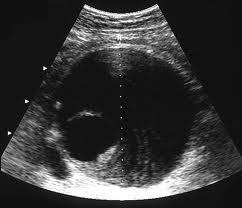

Modern diagnostic tools like ultrasonography (Figure 1) and computed tomography (CT) scan (Figure 2) makes the diagnosis much easier. The reported prevalence is around 4-8% in male and 1-2% in female after 70 year old. With ages beyond 80, the male to female ratio almost became 1:1.

Figure 1. Ultrasonographic picture of AAA